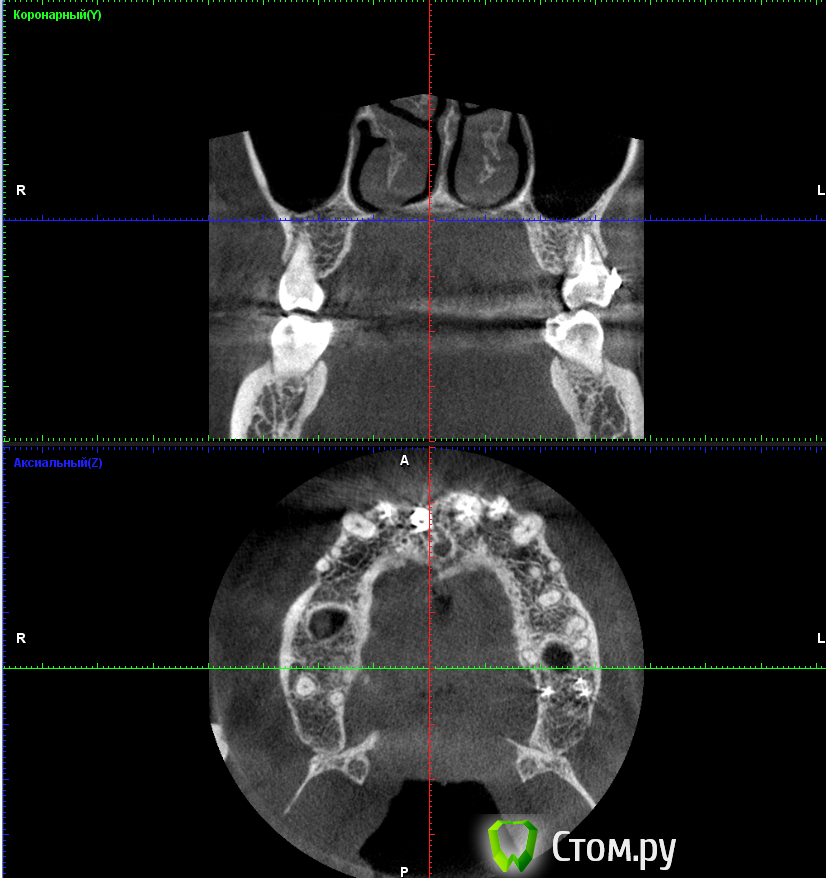

***Irene*** Опубликовано 22 октября, 2014 Поделиться Опубликовано 22 октября, 2014 (изменено) Уважаемые знатоки!Сделали КТ верхней челюсти с имплантом, потому что коронку ну никак не вместить по человечески, десна ходуном ходит, и увидели такую картину (см картинки). То, что имплант стоит слишком глубоко в нёбо и не в зубном ряду - видно даже невооруженным и непрофессиональным взглядом, шейка коронки, как видно на снимке, под большим углом, но коронка все равно торчит вперед.В общем, вердикт доктора - удалять и ставить новый с предварительной аугментацией. Сразу скажу, что в клинике, в которой ставили, клялись, что это нормально, но я оттуда сбежала, вердикт уже из новой клиники.Вопросы:1) На самом ли деле имплант стоит в кости криво?2) Не опасно ли удаление прижившегося импланта и какие могут быть последствия?3) Какова последовательность в данном случае: удаление+аугментация, затем новая имплантация через полгода, затем коронка через полгода? Изменено 22 октября, 2014 пользователем ***Irene*** Ссылка на комментарий

anvladd Опубликовано 23 октября, 2014 Поделиться Опубликовано 23 октября, 2014 (изменено) на 3 кт видно что он косо стоит. Изменено 23 октября, 2014 пользователем anvladd Ссылка на комментарий

***Irene*** Опубликовано 23 октября, 2014 Автор Поделиться Опубликовано 23 октября, 2014 Ну, в общем-то, внутри рта это выглядит именно так, как на 3 КТ - смещение из зубного ряда, причем, нормальное такое. Врач говорит, что это из-за того, что на КТ 4 недостаток кости с внешней стороны и что процесс будет усугубляться, поэтому нужно нарастить кость, удалив этот имплант, и вставить новый. Фиг с ней, с кривизной, больше волнует вопрос, на самом ли деле там спереди не хватает кости и она может "уйти" окончательно, из-за чего имплант вывалится сам? И не развезет ли мне всю челюсть удалением импланта (ведь он же врос в кость), что потом всякие косметические операции понадобятся и пр. Ссылка на комментарий